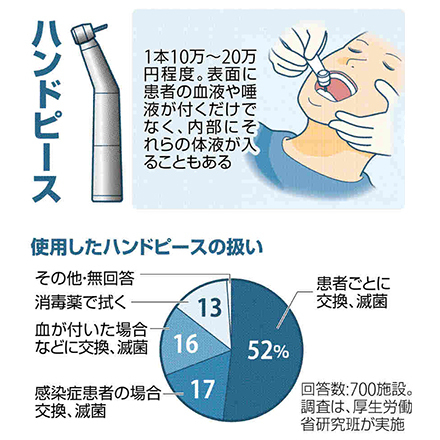

ご存知でしたか

日本に歯科医院の半数以上が

歯を削り機械の使い回しをしていることを!

歯を削る医療機器 半数以上が使い回し・・・

院内感染(血液感染)の恐れという記事がTVやネットニュースで流れていました

2017年7月2日

全国の歯科医療機関の半数近くが、歯を削る医療機器を患者ごとに交換せずに使い回している可能性があることが、2017年の厚生労働省研究班(代表=江草宏・東北大学歯学部教授)の調査でわかった。

実際にタービンヘッドを使用した後の血液が付着したところ

もしこれがB型肝炎やC型肝炎の血が付着し

次の患者に使用しているとしたら・・・

感染症は問診時の自己申告のため、

知らないまま治療していることもあります

そのため、感染症の有無に関わらず

必ず滅菌したもので治療することが必須です